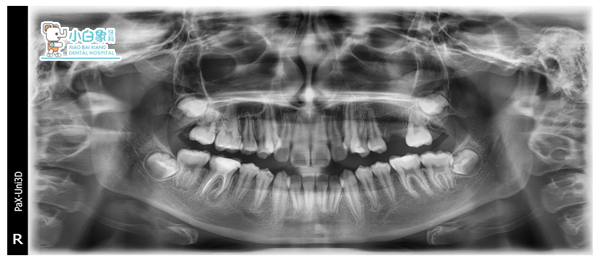

治疗前

X线未见26(已拔除)

46根管见高密度影像,近中根尖处有低密度影像

见18、28、38、48恒牙胚